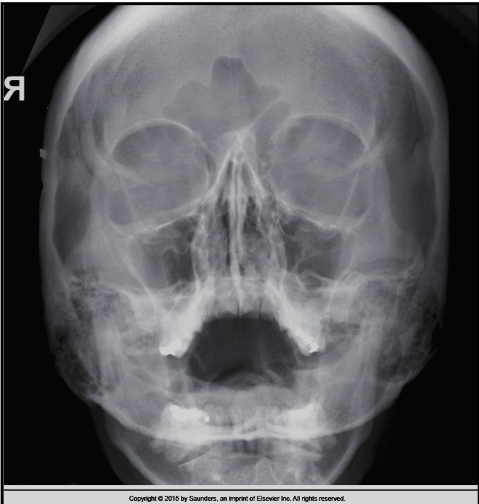

10

Q

what should be corrected about the petrous ridges in this PA cadwell

A

nothing!

11

what are the corrections for this PA caldwell (3)

CP needs to be raised

nose to go right slightly

vertex to go left